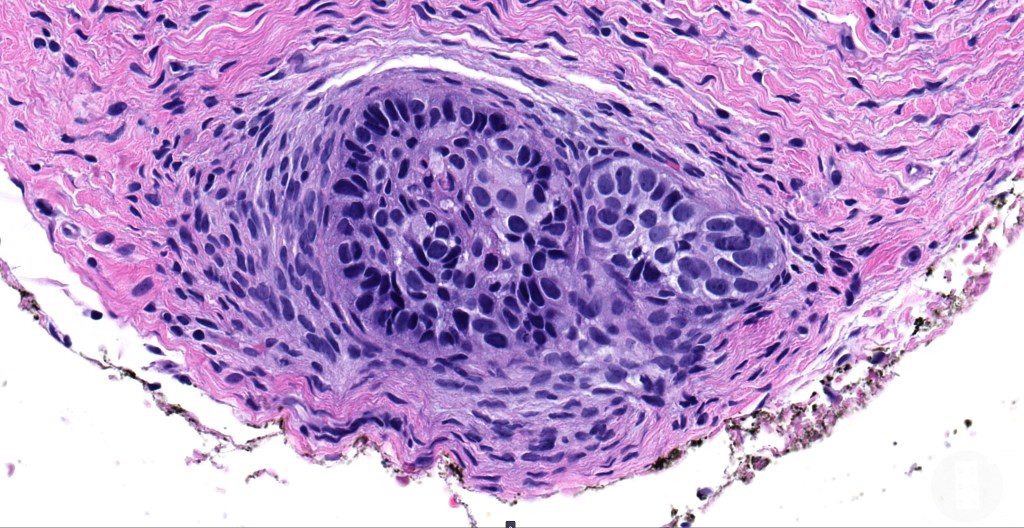

•Low grade trichoblastic carcinoma is easily recognized as trichoblastomatous but shows an infiltrating margin with deep involvement into subcutaneous fat +/- muscle

•High grade trichoblastic carcinoma is characterized by high grade carcinoma arising in a trichoblastoma. TP53 &PIK3CA mutations have been documented